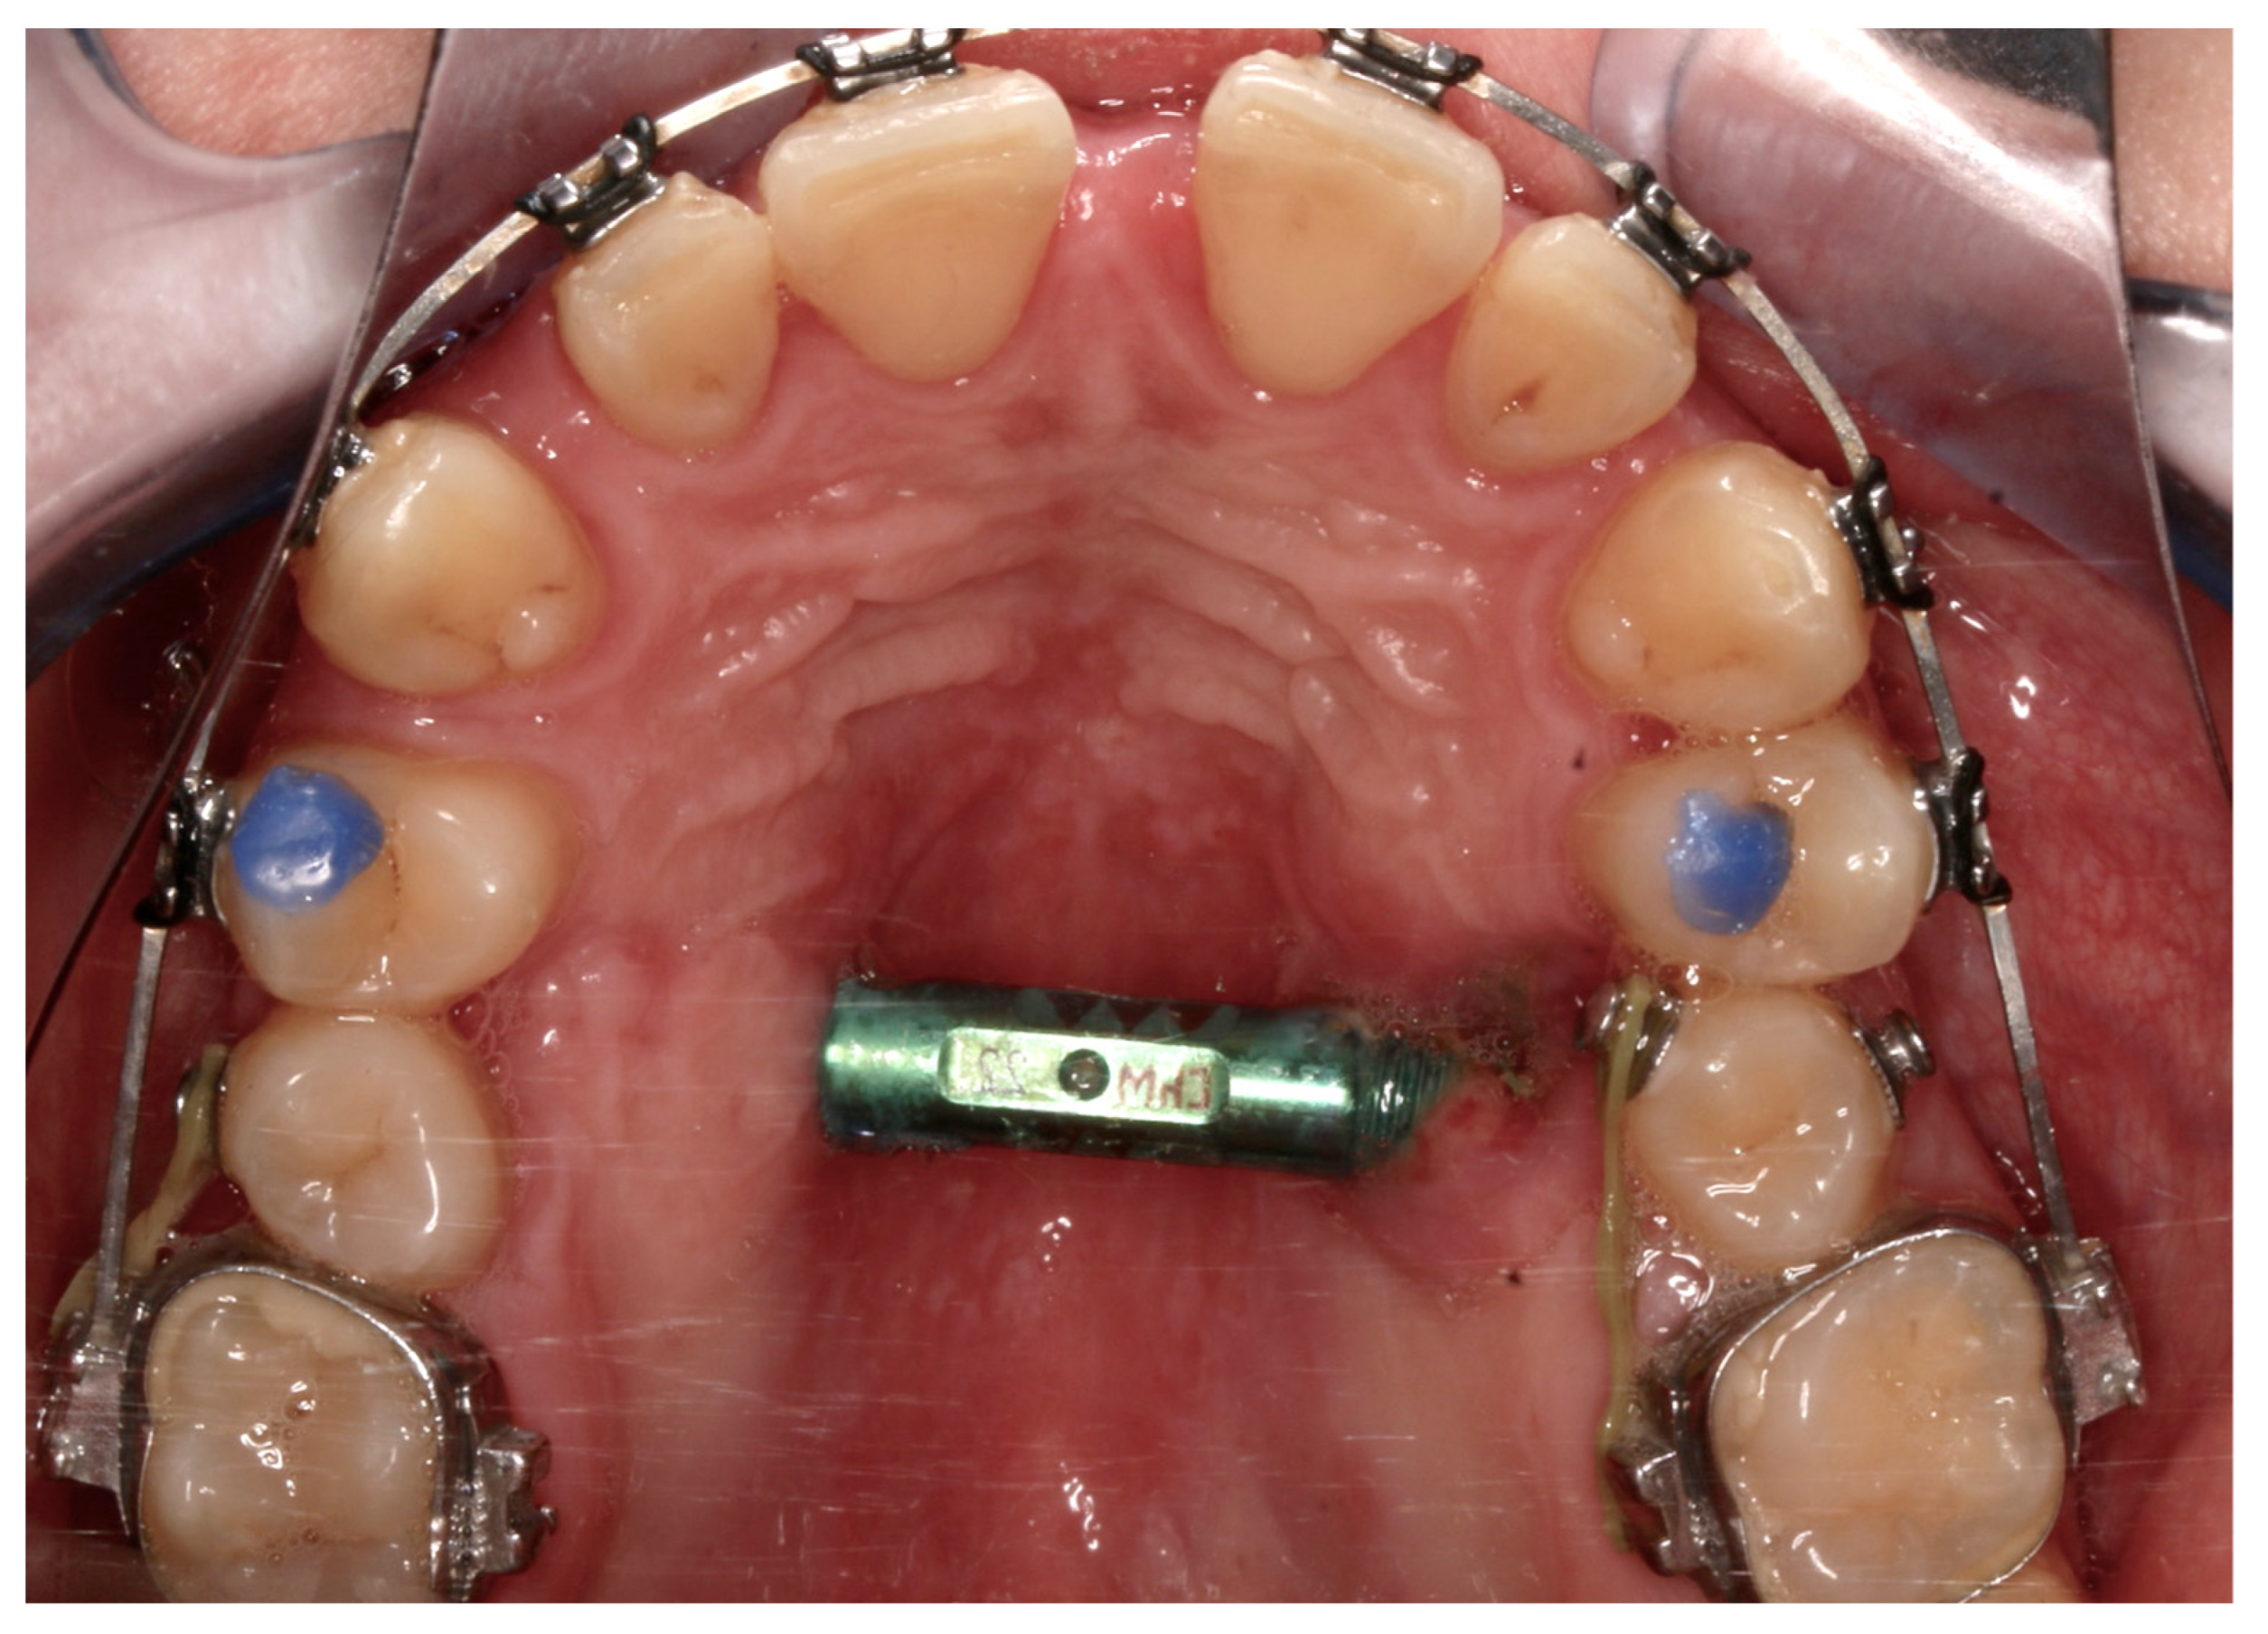

| No possibility of distraction—1 case | Maxillary incisor root resorption—2 cases |

| Palatal mucosal necrosis—2 cases | Bone loss/lack of adhesion in the distraction gap—5 cases |

| Perforation of the maxillary alveolar process caused by the distractor—1 case | Maxillary incisor necrosis—2 cases |

| Asymmetric distraction—5 cases | |

| 9 cases (4.86%) | 9 cases (4.86%) |